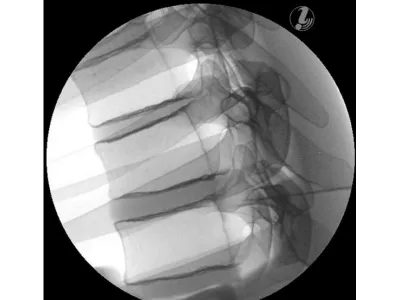

Манекен для инъекций имеет анатомически точную костную структуру (позвонки T3-T8, ребра 3-8) и реалистичную тактильную обратную связь в ходе практики. Кроме того, он выполнен из самовосстанавливающегося материала, который позволяет многократно использовать тренажер.

- Интерламинарная эпидуральная инъекция стероидов

- Трансфораминальная инъекция в грудной отдел

- Дугоотростчатый сустав грудного отдела позвоночника

- Инъекция в нерв (медиальную ветвь)

- Внутрисуставная инъекция

- Блокада межреберных нервов (ICNB)